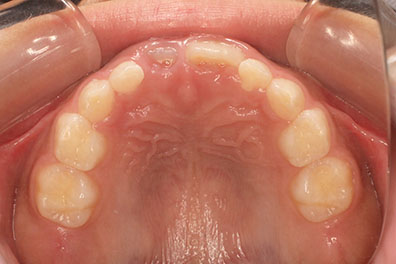

右上の前歯が生えてこない事を気にされ来院されました。 レントゲン写真から、上顎正中に過剰歯が埋伏していることが原因でしたので、抜歯して経過観察。 遅れて、無事に生えてきました。 もし、自然に生えてこない場合は、開窓して、引っぱり出します。(廷出) 状態により、引っぱり出せない場合もあります。 将来的にスペース不足により、上下顎前臼歯部に重度の叢生(がたつき)が予測できますので、がたつきを減らすために、小児矯正で側方拡大を行いました。 小児矯正で側方拡大を行ってもスペースが足りない場合(著しくスペース不足の場合)は、がたつき(叢生、八重歯)が残ります。 残ったがたつき(叢生)は、本格矯正ですべて生え変わった中学生から治せば問題ありません。 来院間隔が平均で1.5カ月でしたので半年ほど治療期間が長いです。